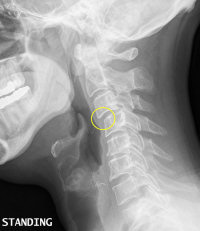

One of the most important considerations for the successful digitization of X-Ray film is image quality. If you plan to purchase an X-Ray film digitizer and digitize the films yourself, then purchase the best X-Ray film scanner you can afford. You will want a digitizer that has clinically proven reliability, image quality, consistency, and overall productivity. The product should be cost effective, lightweight and require little space. Also ask about customer service and support. Vidar, Kodak and Microtek are some of the X-Ray scanner brands that are generally considered to meet the criteria.

If you plan to outsource your X-Ray film digitizing, then find an outsource firm that has the experience of scanning thousands of X-Rays of all types and sizes. They should be able to recognize spots as small as 44mm. They should support most PACS systems and offer direct support of DICOM in order to provide appropriate image compression to avoid bottle necks in imaging. Finally consider HIPAA regulations and patient privacy concerns as well as the appropriate disposal methods of the X-Ray films after they’re digitized.